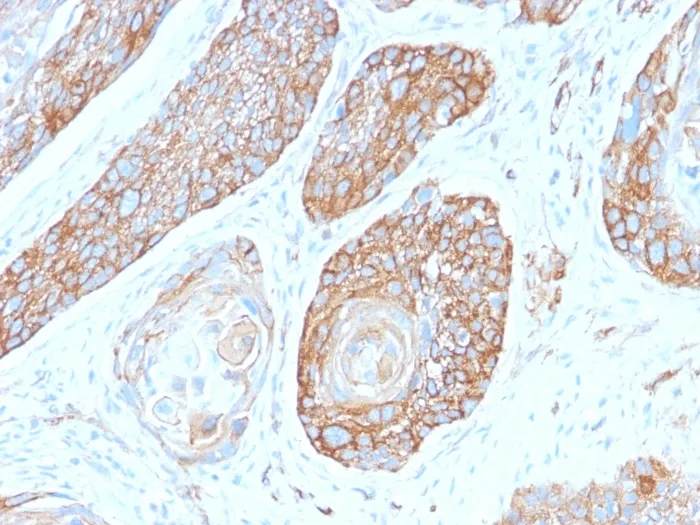

- Applications: IHC, FFPE (verified) | WB (verified)

- Positive Control: HeLa cells. Pancreas or Liver.